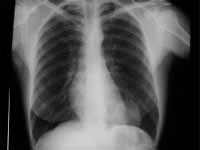

Radiografía de Tórax

Su utilidad puede ser considerada de manera directa o indirecta, es decir depende de si se observa directamente la lesión o si por el contrario encontramos hallazgos radiológicos que nos hagan pensar en la presencia de una masa pulmonar, es por esto que las manifestaciones se relacionan tanto con el tamaño de la lesión, así como por las cambios que éstas puedan producir en el parénquima pulmonar (4).

Dentro de las manifestaciones radiologicas más comúnes tenemos las neumonías postobstructivas, atelectasias lobares o segmentarias, nódulo pulmonar solitario, engrosamiento de las paredes bronquiales, masa pulmonar, alteración en la morfología del hilio, compromiso pleural (engrosamiento, derrames), ensanchamiento mediastinal (3,4,23,25,28).

Figura 8. Masa pulmonar basal izquierda

Si bien la radiografía de tórax es altamente sensible en la identificación de estas alteraciones, es mucho menos específica. Estas alteraciones se puede asociar a otras patologías. Es por eso que su relación con la clínica y los antecedentes del paciente son de suma importancia en la interpretación de estos hallazgos.

De otro lado, es este el método de entrada en el estudio de lesiones pulmonares sospechosas, pero no el final, es por eso que las otras técnicas imagenológicas han venido adquiriendo una mayor importancia en el estudio de las neoplasias pulmonares.